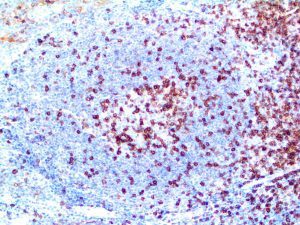

It is the ICU physician who is most likely to witness one of the deadliest manifestations of the abnormal immunological response, the cytokine storm syndrome (CSS). This response is also referred to by some as the cytokine release syndrome (CRS). CSS is characterized by continuous activation and expansion of macrophage and lymphocyte populations, which secrete large amounts of cytokines, causing the cytokine storm. This massive cytokine release is akin to hemophagocytic lymphohistiocytosis (HLH) disease, a syndrome characterized by initial unchecked and persistent activation of cytotoxic T lymphocytes and NK cells.

Clinical and laboratory manifestations of HLH include fever, enlarged liver and/or spleen, neurologic dysfunction, coagulopathy, liver dysfunction, cytopenias (i.e., low levels of erythrocytes, leukocytes, and/or platelets), hypertriglyceridemia, hyperferritinemia, hemophagocytosis, and eventually diminished NK cell activity as the immune system becomes progressively paralyzed. HLH can be familial (primary HLH) or secondary to another disease process (sHLH), such as rheumatic disease, in which it is referred to as macrophage activation syndrome (MAS, characterized by elevated ferritin).